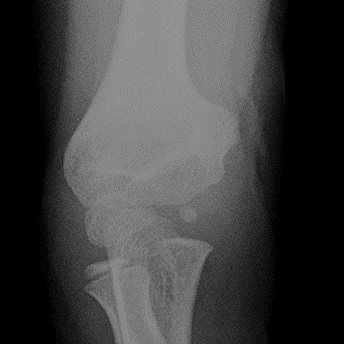

- 肱骨外髁骨折發生於小朋友手肘骨頭還在發育的情況,所以x光下不是很明顯,常常造成誤診,如果未能及時治療,常常可能造成肘關節變形,或骨癒合不良。

- 此骨折是小朋友少數會發生骨不癒合的部位,需小心謹慎處理!